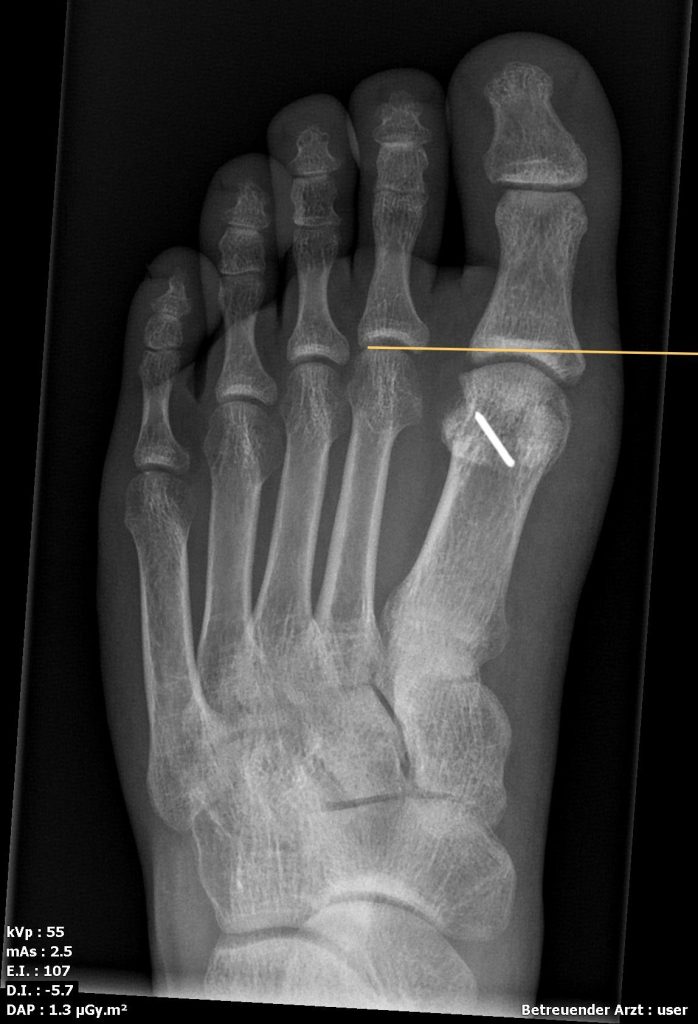

Youngswick Osteotomie

(Arthrose Gelenkspalt mehr als 50%, langer erster Mittelfußknochen)

Ist eine Modifikation der Chevron-Osteotomie ( OP bei Hallux valgus) dabei wird eine V- Förmige gelenknahe Durchtrennung des ersten Mittelfußknochens durchgeführt . ( in Kombination mit einer Cheilotomie) und eine Knochenscheibe entnommen, dadurch kommt es zu einer Verkürzung des ersten Strahls und einer Druckentlastung des Gelenks, was einer Verbesseerung der Beweglichkeit und Reduzierung der Schmerzen führt. Diese Operation führen wir häufig bei noch erhalten Gelenkspalt als Alternative zur Versteifung durch.

- Röntgen zur Beurteilung von Gelenkspalt, Osteophyten, Stellung